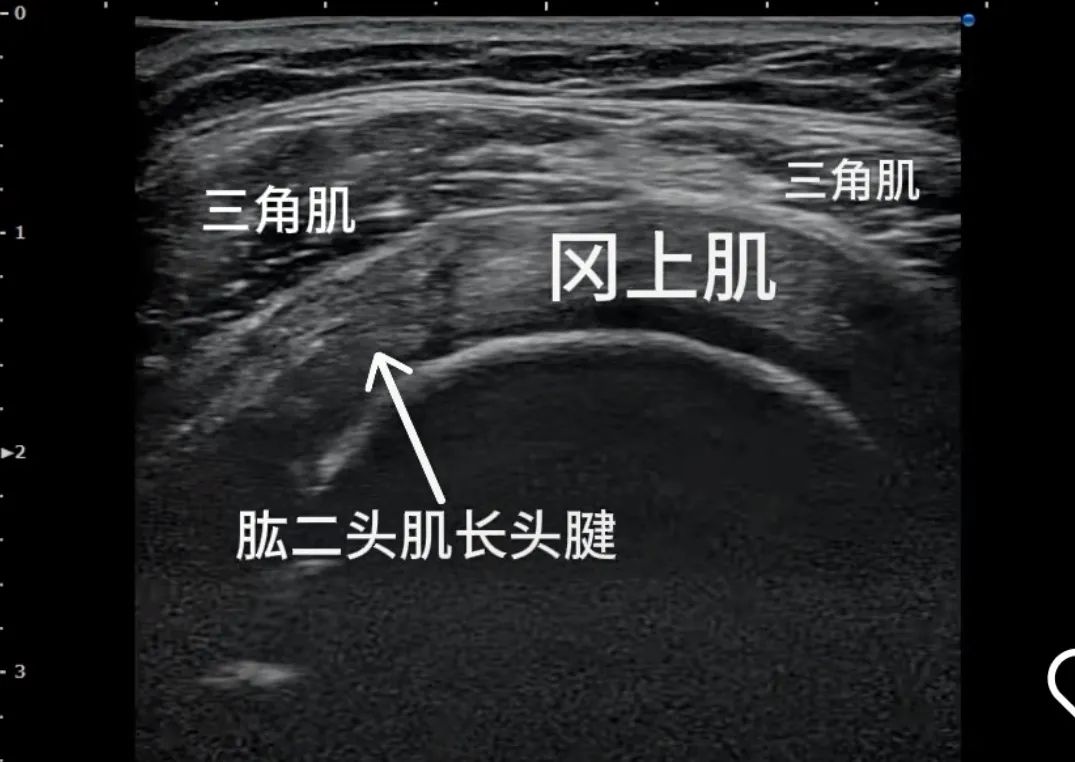

采用肌骨超声,能够清晰显示关节、肌肉、肌腱、韧带、周围神经、筋膜等软织结构及其发生的病变。超声引导下精准治疗可以清晰显示针尖位置、进针路径中的重要结构,明确将药物注入病变区域,解除病痛的同时能减少药物的使用量,也能避免伤周围血管、神经。

王主任形容,健康的肩关节囊像充气的气球,冻结肩患者的关节囊,已经挛缩成一条干瘪的皮带,通过肩关节腔灌注扩张治疗,就像向干瘪的气球里注水,通过扩张撑开粘连的关节囊,可以让关节囊再次膨胀起来,恢复它正常的容积,同时药物成分可以精准作用于病变区域,消炎止痛,抑制纤维化进展,让冻结肩患者获得症状减轻的体验感,可以达到明显的治疗效果。